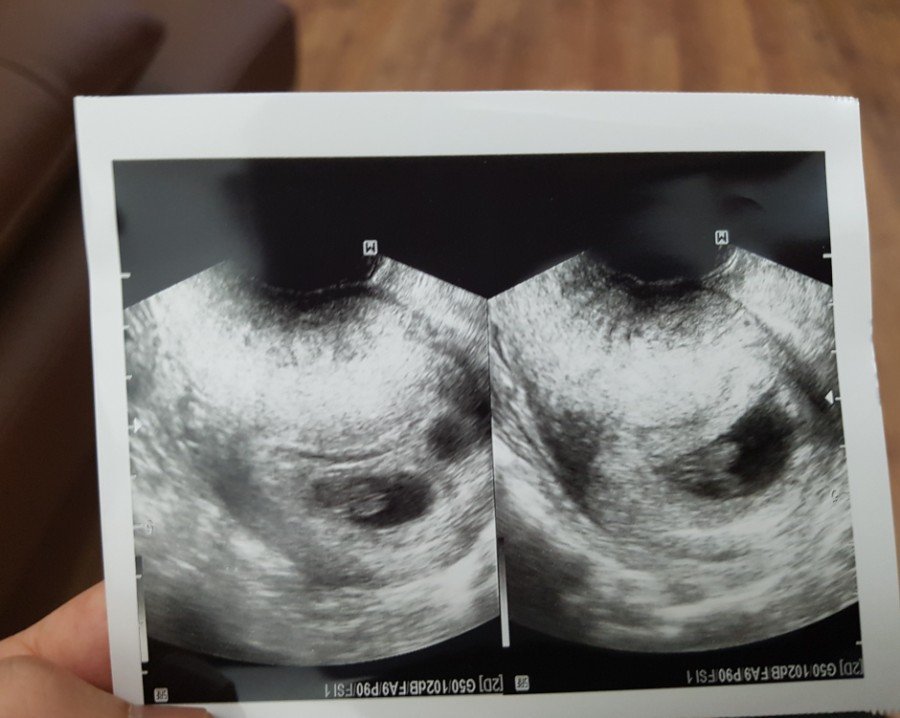

열심히 살았구나

20180328_203042.jpg

열심히 분열 중인 얼렁뚱땅_

엄마아빠만 노력한 게 아니라

너희들도 많이 애썼다.

기특해, 아가들_

젤리곰은 성장 중

20180328_190042.jpg

젤리곰에서

가제트팔처럼 어느새 팔다리가 쑥_

한 주 한 주 조금씩 성장하는 너희를

엄마아빠가 아주 많이

응원해.